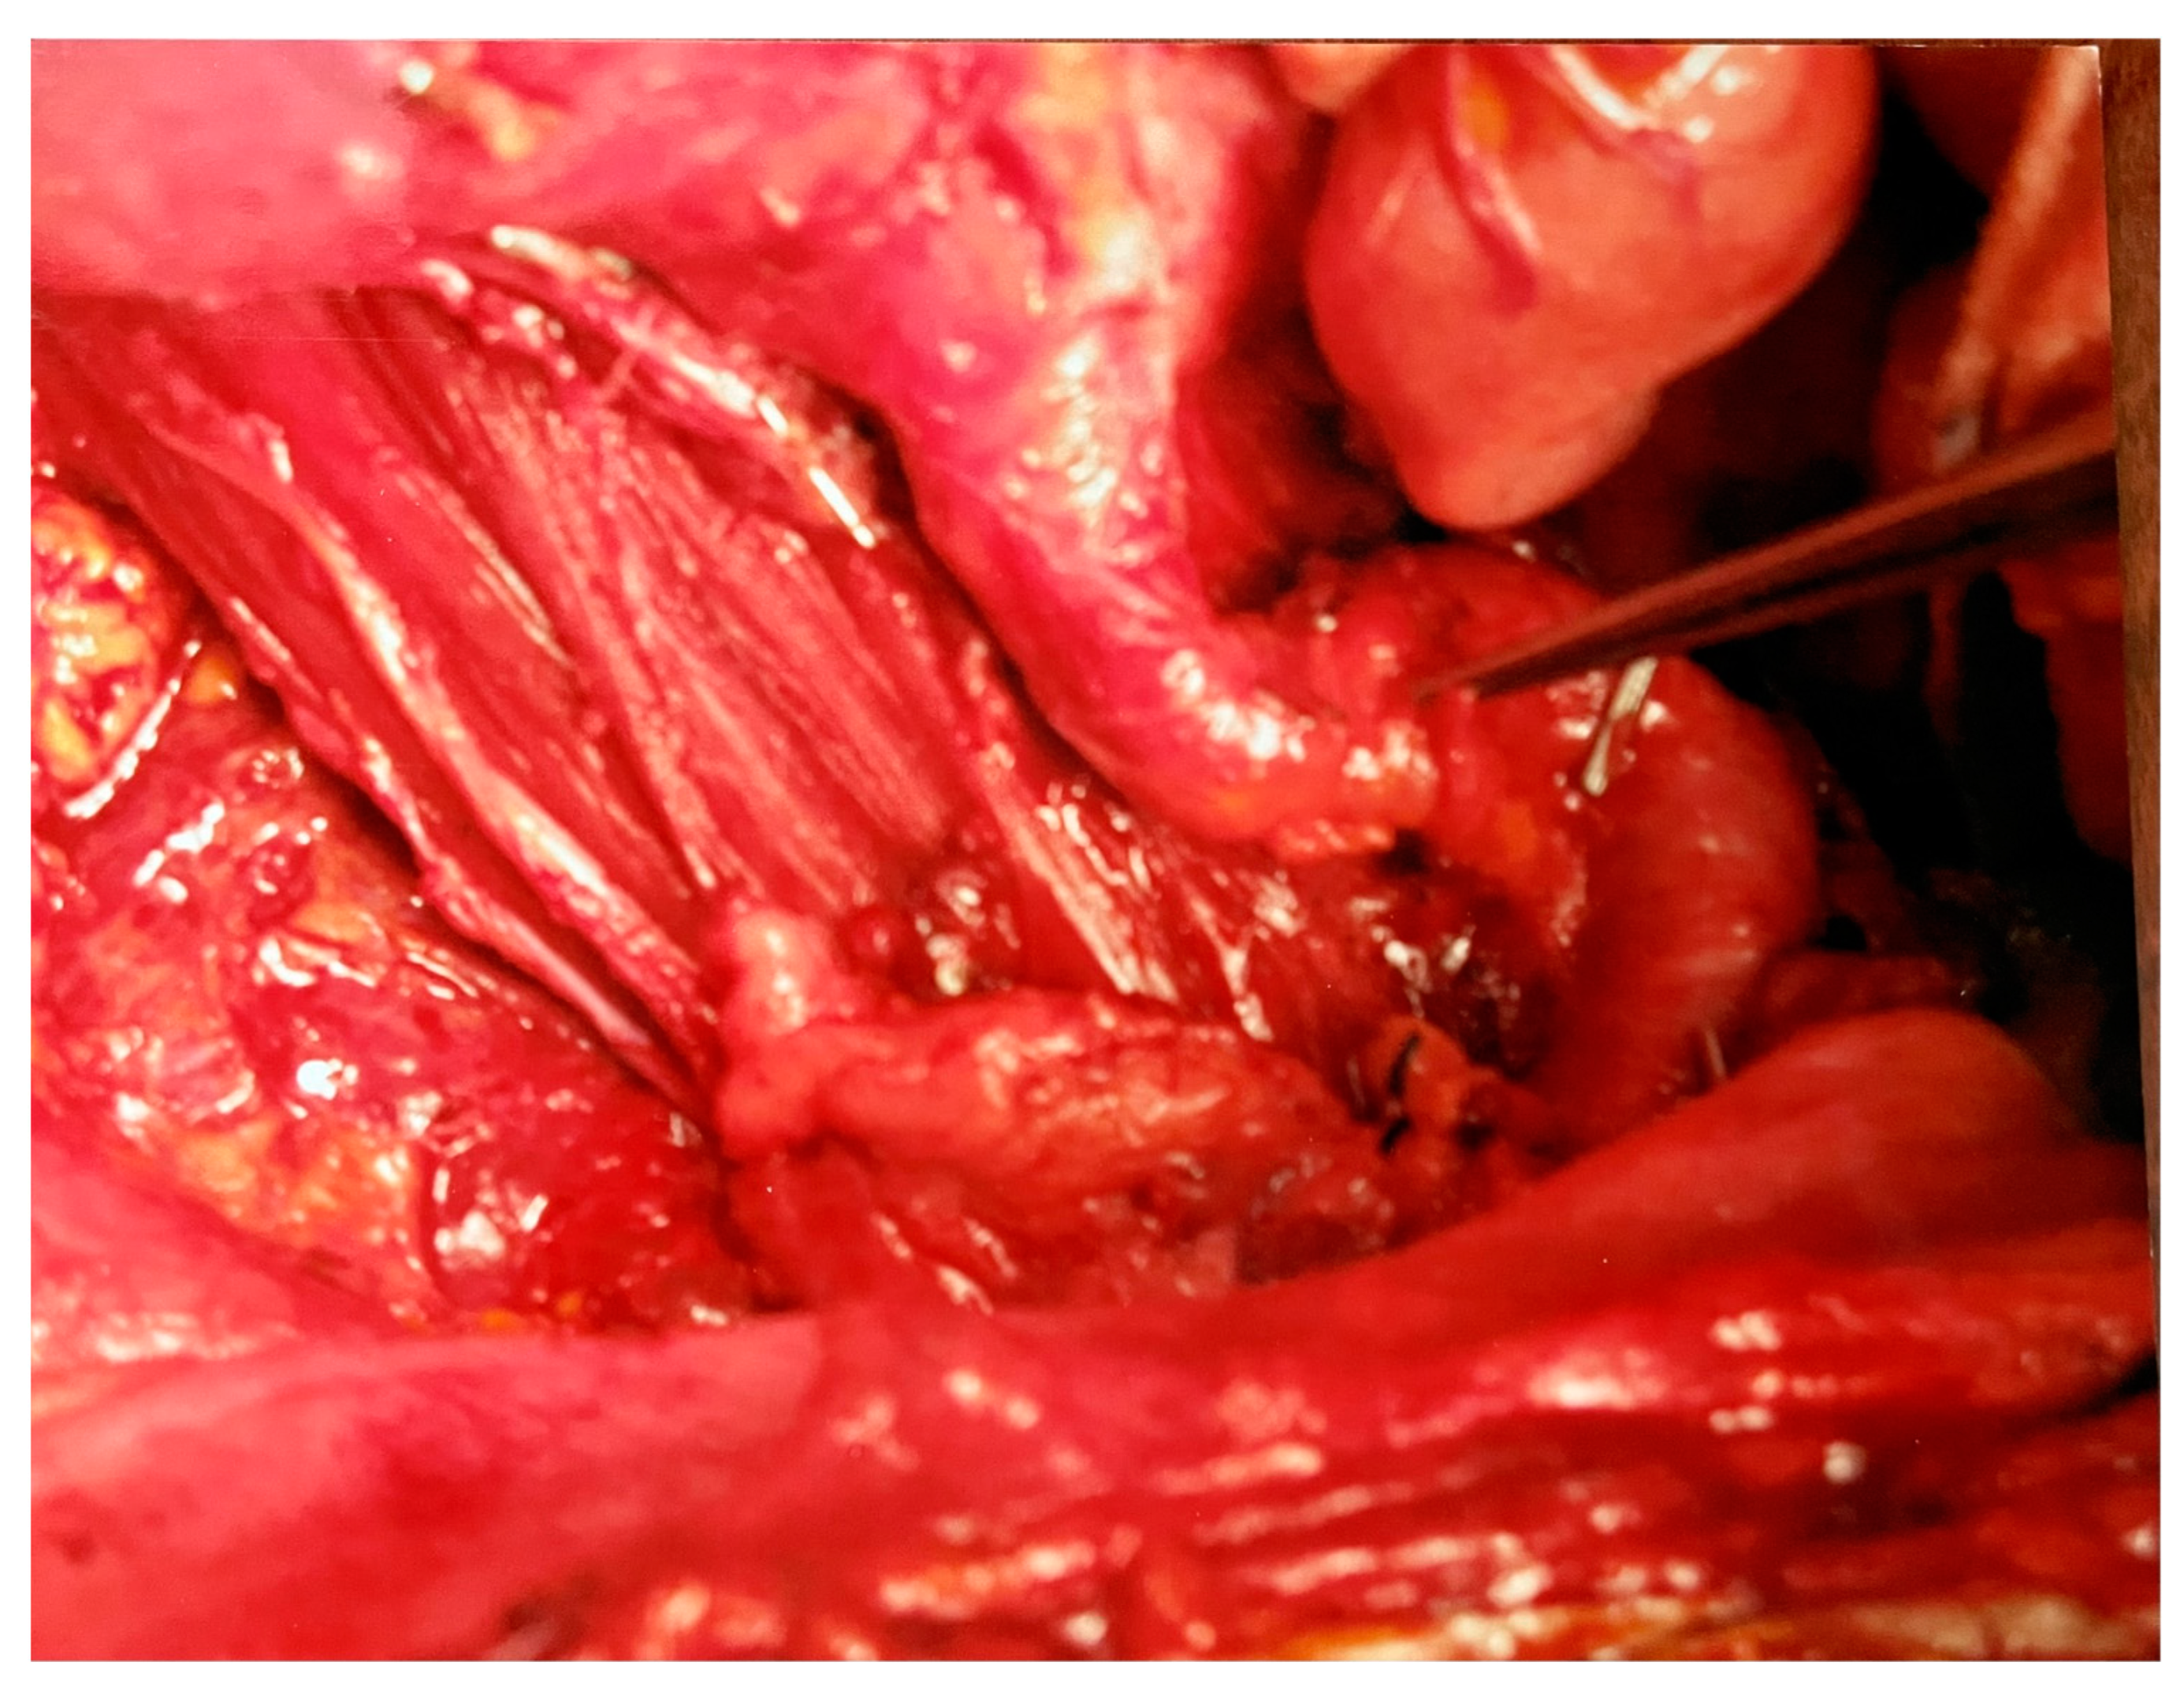

Figure 2. Tumor Retraction for Visibility.

2.7. Actual Outcome

During the surgery, a huge tumor mass involving and deviating towards the right retroperitoneal structures including the colon, duodenum, and vascular structures—anterior and to the left—was found. During surgery, we were able to encircle and remove a major en bloc portion of the tumor (greater than 13.5″ or 35+ cm in cross section and greater than 38″ or 98 cm in diameter) along with a portion of the right colon (Figure 1, Figure 2 and Figure 3). Her weight, after surgical resection, dropped from 125 pounds to 79 pounds. The excised tumor mass overflowed and covered the entire surgical scrub basin margins. Following an uncomplicated recovery, she regained her weight and returned to work as a supervisor.

During the multiple surgical procedures, this patient had approximately 120 pounds of liposarcoma removed. The photographs demonstrate the enormity of one of the tumor resections and the surgical difficulty encountered during the resection. We were able to monitor the tumor progress palpably and with recurrent X-rays, computerized tomography scanning, and ultrasounds, and to periodically palliate the disease process surgically, but we were not able to cure the tumor. None of the referenced articles discussed a loss of renal function due to tumor encroachment as being related to the demise of the patient.

4. Conclusions

This patient was aware of her diagnosis (a huge recurrent liposarcoma of the retroperitoneum) and prognosis when initially seen by us for palliative care. But, after some discussion, despite her diagnosis, we were able to provide options and a treatment program enabling her to return to productive employment for more than a decade. She elected to follow a palliative course, which provided her with many years of fruitful employment as well as the enjoyment of her family and friends. Despite her diagnosis and the rigors of treatment, as exemplified by the photographs, she had very positive surgical palliative results until the potential need for chronic dialysis after the completion of a nephrectomy and pancreatectomy.